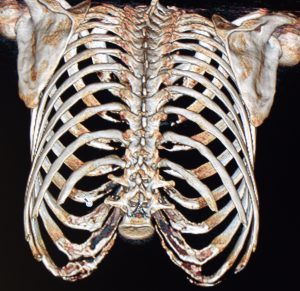

With rib 10 now considered standard treatment, the next logical and evolving question is whether rib 9 can also be addressed. Rib 9 is a typical rib, similar in morphology to ribs 3 through 8, with a long, curved, flattened shaft and an anterior attachment to the subcostal cartilages. It corresponds anatomically to the upper abdominal region and the inferior margin of the thoracic cage. Deep to rib 9 lie the liver on the right and the spleen on the left; more critically, the pleura of the lung lies immediately beneath it.

With an understanding of the rib–lung relationship, rib 9 can be surgically treated, but the method becomes the central question—removal versus fracture. A fracture technique is not feasible because the distal end of rib 9 is rigidly attached to the costal margin. Complete removal of four ribs (9, 10, 11, and 12) would be ill-advised, as it would leave a large unsupported area of the chest wall bilaterally.